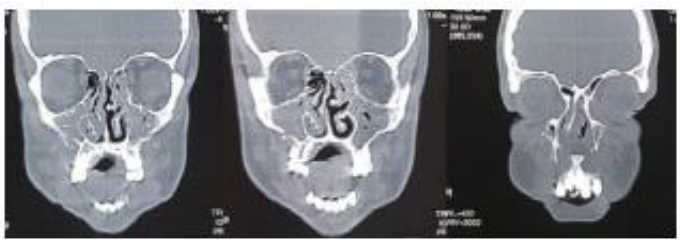

M.A., 32 anos, é atendido no Pronto Atendimento do Hospital Regional, vítima de colisão auto-moto. Ao exame físico: Desorientado, Pupilas Isocóricas e com reflexos pupilares preservados, edema de face, múltiplas escoriações, hematomas na região frontal e malar bilateral, afundamento do dorso nasal, epistaxe bilateral, ao exame da cavidade oral: fratura dos incisivos centrais superiores e presença de mobilidade da maxila. A partir dessas informações e após a análise do seguinte exame de imagem abaixo, assinale a alternativa que contém o diagnóstico:

Enunciado 3621133-1